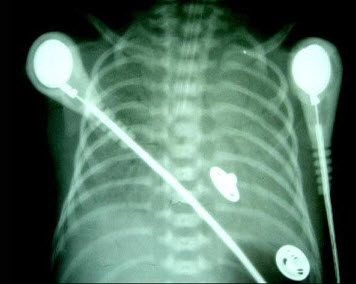

290、单项选择题

新生儿出生后出现气急、口吐白沫,呼吸微弱。床边X光片检查如图,最可能的诊断为()

A.新生儿肺炎

B.新生儿肺出血

C.新生儿白肺

D.新生儿心肌炎

E.先心病

291、单项选择题 引起肝内胆管、胆总管、胰管扩张,胆囊肿大的病变是()